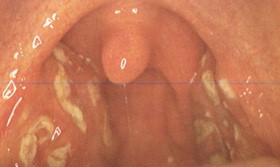

You are shown a x-ray of the chest and abdomen and a photograph of the oropharynx

(see panels A and B below) of a 19-year-old women whose chief complaints include,

fever, malaise, and sore throat of 7-days duration. You are given no other information.

Panel B. The exudative on the patient's tonsils has the characteristic color (yellow to greenish

yellow) of EBV infection; this is in contrast to adenoviral and streptococcal exudates

which, in the experience of the Editor, are white and white-to-grey, respectively.

The patient does not have a Forscheimer's sign (palatal petechiae) which may be seen

in EBV-MN, streptococcal tonsillitis, rubella, rubeola and scarlet fever.